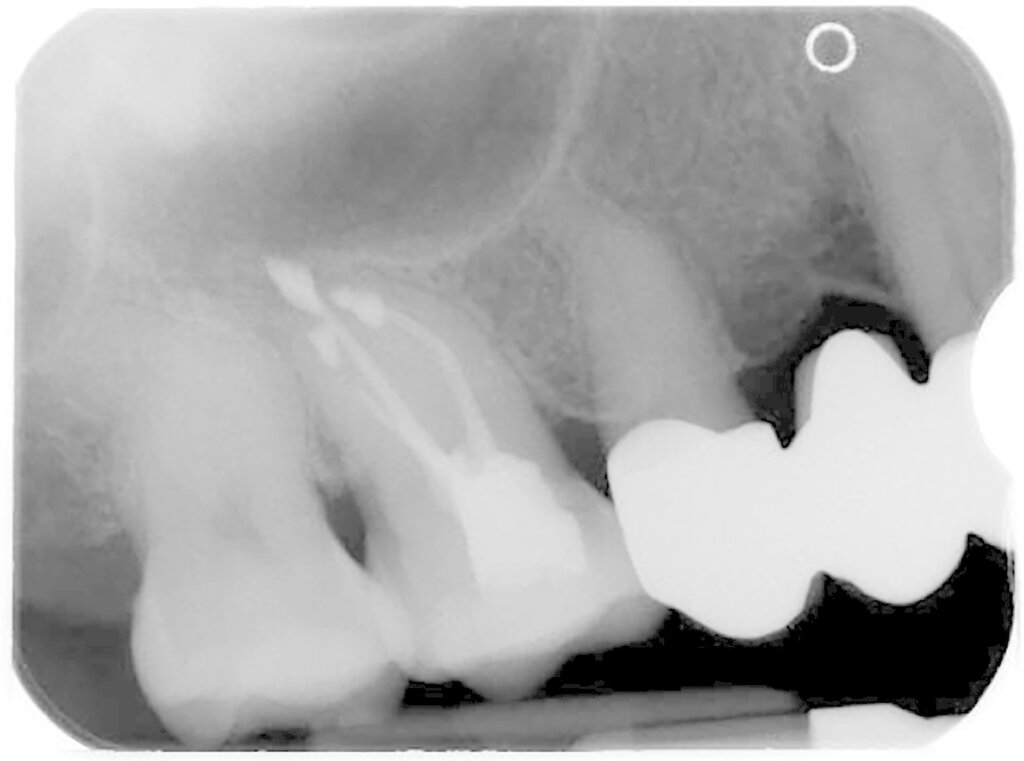

Eine präoperative akute klinische Symptomatik in Form von Schmerzen, Perkussionsempfindlichkeit, einer Schwellung oder einem Abszessgeschehen ist mit einer signifikant schlechteren Prognose des Zahns vergesellschaftet. Gleiches gilt für das Vorhandensein einer Fistel bei chronischem Verlauf. Zähne, die zum ersten Mal einer WSR unterzogen werden, haben eine signifikant bessere Prognose als Zähne mit einer Revision der WSR. Ein weiterer wichtiger prognostischer Faktor sind retentive Wurzelstifte (Abbildung 3). Die besondere Problematik bei diesen Zähnen liegt oftmals in der erschwerten Möglichkeit der apikalen Abdichtung, wenn der Stift bis zum Neoapex reicht. Infolgedessen werden die Wurzeln oft weniger stark gekürzt, um noch ausreichend Wurzelkanal für die retrograde Wurzelfüllung zu haben. Zum anderen werden in dieser Gruppe auch in der Folgezeit Wurzelfrakturen häufiger beobachtet. Dies scheint insgesamt von Relevanz zu sein, denn diese Zähne haben ebenfalls eine signifikant schlechtere Prognose. Zähne mit einer Stiftperforation stellen ohnehin eine Kontraindikation für eine WSR dar und sind hier gar nicht berücksichtigt.

Bezüglich der Zahnlokalisation zeigen eigene Zehn-Jahres-Daten signifikante Unterschiede zugunsten des Oberkiefers. Bei der differenzierteren Betrachtung von Frontzähnen, Prämolaren und Molaren zeigte der paarweise Vergleich signifikante Unterschiede zwischen den Molaren und den Frontzähnen sowie den Molaren und den Prämolaren. Die Unterschiede zwischen Frontzähnen und Prämolaren waren nicht signifikant [Kreisler et al., 2018]. Bei diesem Phänomen handelt es sich möglicherweise mitunter um ein statistisches Problem. Betrachtet man nämlich jede einzelne Wurzel als Lokus des potenziellen Scheiterns, steigt natürlich das Gesamtrisiko bei einem mehrwurzeligen Zahn. Das Vorhandensein von Isthmen als Ursache wurde in der Literatur diskutiert [Kim et al., 2016]. Allerdings stellt das Erkennen von diesen und deren Einbeziehen in die Präparation und Abdichtung heutzutage eigentlich eine Selbstverständlichkeit dar (Abbildung 4). Gleiches gilt für die Berücksichtigung der palatinalen Wurzel bei Oberkiefermolaren.